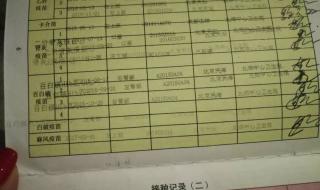

五、lol剑圣打野符文

1、LOL剑圣打野符文如下:

2、1,红色固定攻击力。

3、2,黄色固定护甲。

4、3,蓝色成长魔抗。

5、4,大精华攻击速度或者固定攻击力。英雄联盟游戏中,野怪的伤害全部为物理伤害,因此选择护甲符文能够降低野怪伤害,适当提升攻击力和攻击速度能够大大提高刷野效率。